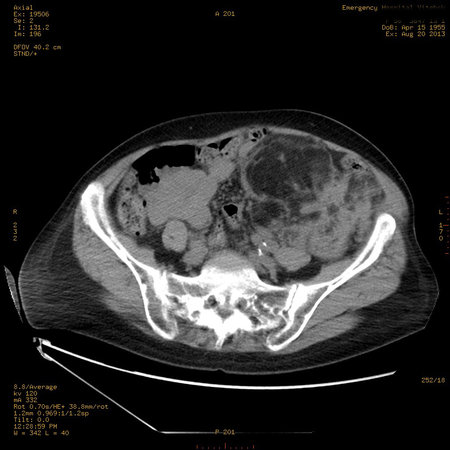

Пожилая женщина с нормальными мочевиной и креатинином.

Ангиомиолипоматоз почек , думаю компонент туберозного склероза.

Да, туберозный склероз.

Случай консультирован на кафедре радиологии Католического университета г.Лёвен (Бельгия) - зав каф. профессор Р.Оуен.